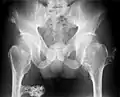

-

Multiple osteochondromas at the pelvis -